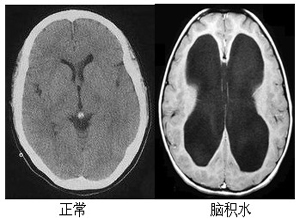

先天性腦積水是由于先天性畸形引起的,比如說(shuō)臨床上常見(jiàn)的中腦導(dǎo)水管狹窄及閉塞、小腦扁桃體下疝及第四腦室中孔或側(cè)孔閉鎖等等,一般這種疾病的主要癥狀表現(xiàn)為嬰幼兒砸出生后數(shù)周之內(nèi)頭顱開(kāi)始增大,特別是由于顱內(nèi)壓力較大導(dǎo)致頭顱的比例與身體出現(xiàn)嚴(yán)重的不協(xié)調(diào),不僅患者面部特征會(huì)出現(xiàn)額部向前突出、雙眼球下視,眼球向下轉(zhuǎn)的情況,一些患者還會(huì)導(dǎo)致腦發(fā)育障礙或者是癱瘓等嚴(yán)重情況,那么先天性腦積水能活多久呢?

腦積水患者的生存時(shí)間取決于病情的發(fā)展階段和治療情況。腦積水這種病在過(guò)去死亡率很高,治愈難度較大,但隨著科技的發(fā)展,近年來(lái)一些腦積水患者可以治愈 ,并不影響智力,預(yù)后較好。